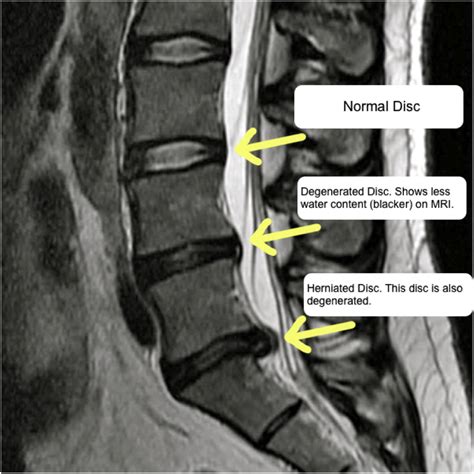

At its core, multilevel discogenic disease refers to the structural degradation of multiple spinal discs. Your intervertebral discs act as shock absorbers between the vertebrae, maintaining spinal flexibility and height. Over time, these discs may lose their water content, become brittle, or bulge, leading to a loss of space between vertebrae. When this occurs across multiple levels (e.g., in the cervical or lumbar regions), it is classified as a multilevel condition.

MRI Scan The "gold standard" to visualize discs, nerves, and soft tissue.